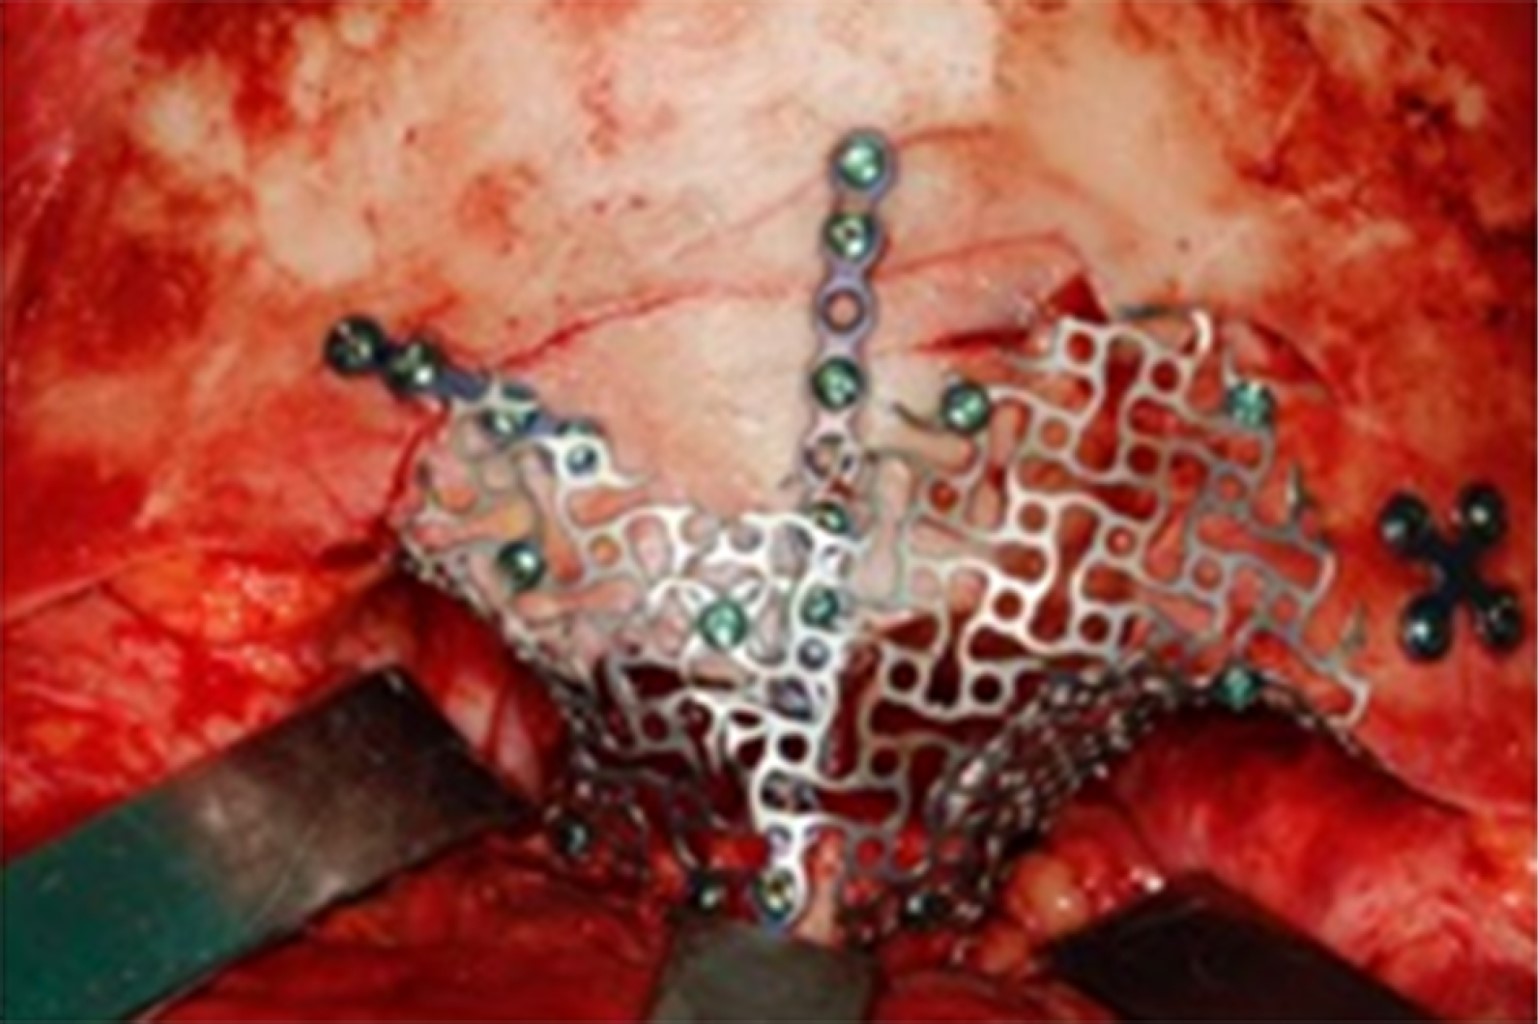

Bajo anestesia general, el paciente fue intervenido cinco días después del traumatismo para la reducción y fijación de las fracturas realizando un acceso bicoronal (Figura 1), infraciliar bilateral, sutura frontozigomática del lado izquierdo y acceso intraoral de Caldwell-Luc en fondo del saco superior del lado derecho. Las fracturas orbitarias bilaterales se reconstruyeron con malla de titanio en el suelo, la pared medial y el techo orbitario; todas las fracturas se fijaron con placas y tornillos del sistema de 1.5 mm; se realizó una prueba de ducción forzada con pinzas Adson y la movilidad del globo terráqueo fue satisfactoria (Figura 2).

En la tomografía computarizada postoperatoria de la cara se puede observar la reconstrucción de las fracturas del seno frontal, del techo, de la pared medial y del suelo orbitario y sus respectivas fijaciones (Figuras 3 y 4).